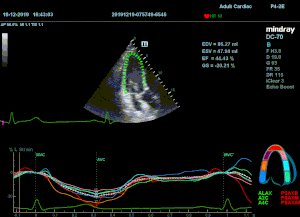

Всё изменилось с появлением технологии Speckle-tracking. Ультразвуковые приборы компании Mindray DC 8, 70, 80, Resona 6,7 оснащены данной функцией. Для использования необходим ЭКГ-канал. В чем же смысл данного технологического новшества? Прибор использует видео петли сечений миокарда, разбивает миокард на точки со стабильной визуализацией – speckle, и затем производит слежение каждой точки в течении нескольких сердечных циклов. Изменение пространства между точками дает нам представление о возможностях деформации миокарда, как продольной – Longitudinal Strain, так и деформации скручивания – торсии и Radial Strain.

На сегодняшний день в мировой клинической практике используется продольный Strain. Методика позволяет выявить нарушения в работе миокарда в каждом отдельном сегменте в среднем до 5 лет раньше клинического манифеста. Так же есть возможность оценки и диастолической функции, с гораздо более высокой чувствительностью чем тканевой допплер. Возможности радиального стрейна изучаются, за этой методикой будущее.

Как работать с данным методом? Для Longitudinal Strain необходимо записать видео петли апикальных сечений в память прибора: 4С, 3С, 2С. Для повышения качества трекинга рекомендуется производить запись на выдохе пациента. Затем произвести разметку по линии эпикарда, перикарда и центра миокарда. Нажатием кнопки «начать слежение» активируется программный алгоритм, видео петля оживает вместе с размеченными точками-speckle’ами. При необходимости производится коррекция. После анализа всех трех сечений можно получить данных продольной деформации как в среднем значении, так и по каждому сегменту миокарда левого желудочка. Нормальным показателем считается Longitudinal Strain -20%. Нижней границей -14%.

Видео примеры на приборе Mindray DC 70